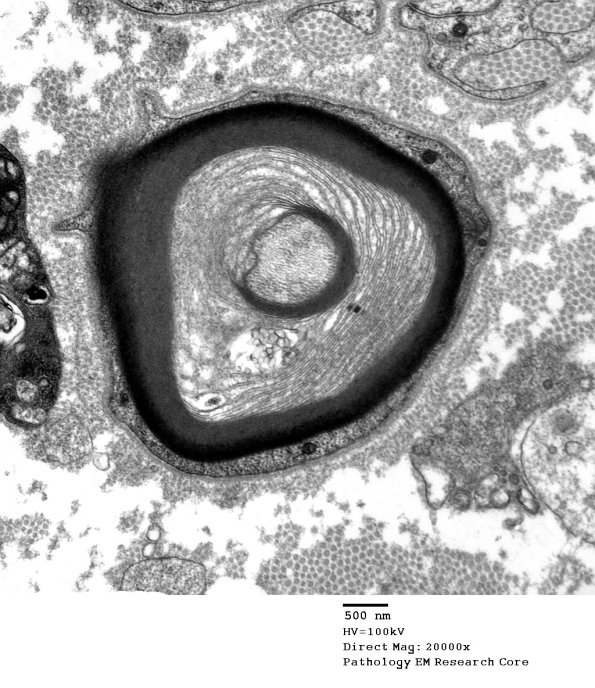

Several magnifications of the UCM in this lesion are demonstrated as well as a hemidesmosome like focus. (electron micrographs)